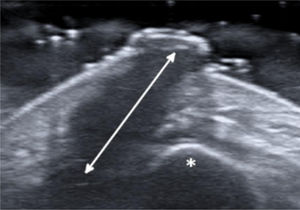

A 27-year-old female patient presented with a six-month history of a persistent and painful nodule on the chin. She referred occasional purulent exudate. There was no history of fever or systemic symptoms. Several courses of oral antibiotics had been ineffective. In the extraoral examination she presented an erythematous nodule with an important surrounding retraction (Fig. 1). Ultrasonography (Esaote MyLab Gamma®, 18 MHz) revealed a hypoechoic lesion with increased blood flow in the base and periphery. Moreover, an inflamed tortuous sinus tract extended through the subcutaneous tissue to the alveolar bone (Fig. 2). These findings were consistent with an odontogenic cutaneous fistula (OCF). A panoramic radiograph showed its origin in a mandibular incisor (Fig. 3). The patient was referred to the Maxillofacial Surgery Department of this hospital for assessment and treatment. Dental extraction was suggested in order to remove the source of the infection.

The diagnosis of OCF is usually made based on panoramic radiograph and computed tomography that show the damage of the alveolar process. However, these tests require considerable time and money to perform and may have side effects. Skin ultrasonography is a noninvasive and emerging technique with proven usefulness in localized lesions.3 High frequency imaging not only provides robust qualitative and quantitative information on skin lesions but also on their surrounding tissues. Moreover, color Doppler ultrasonography gives information about its vascularization. Therefore, this technique has been found really useful in the diagnosis of cutaneous sinus tracts. Ultrasound image of OCF consists of a hypoechoic linear but slightly tortuous sinus tract that reaches the cortical bone, with an increased blood flow in the peripheral regions of the tract.4,5 Most of these features characterize this lesion and easily distinguish it from other pathologies included in the clinical differential diagnosis. Regarding its treatment, antibiotic therapy brings an apparent healing, but if the source of infection is not eliminated, the sinus tract recurs in time. It is believed that high-frequency ultrasonography could also be useful in monitoring response to treatment by showing a decrease in the vascularization and a progressive reduction of the sinus tract. In addition, it could also allow the detection of early recurrences. In order to accomplish resolution, therapy has to focus towards the management of the dental infection, either with endodontic treatment or extraction.2 Surgical excision of the sinus tract is not usually necessary, as it heals spontaneously after the dental treatment.

Skin ultrasound is a safe and accessible tool for the diagnosis of OCF. The characteristic image of a hypoechoic sinus tract enhanced by color Doppler enables its diagnosis. Hence, neoplastic lesions are rapidly discarded, and many inappropriate treatments are avoided.